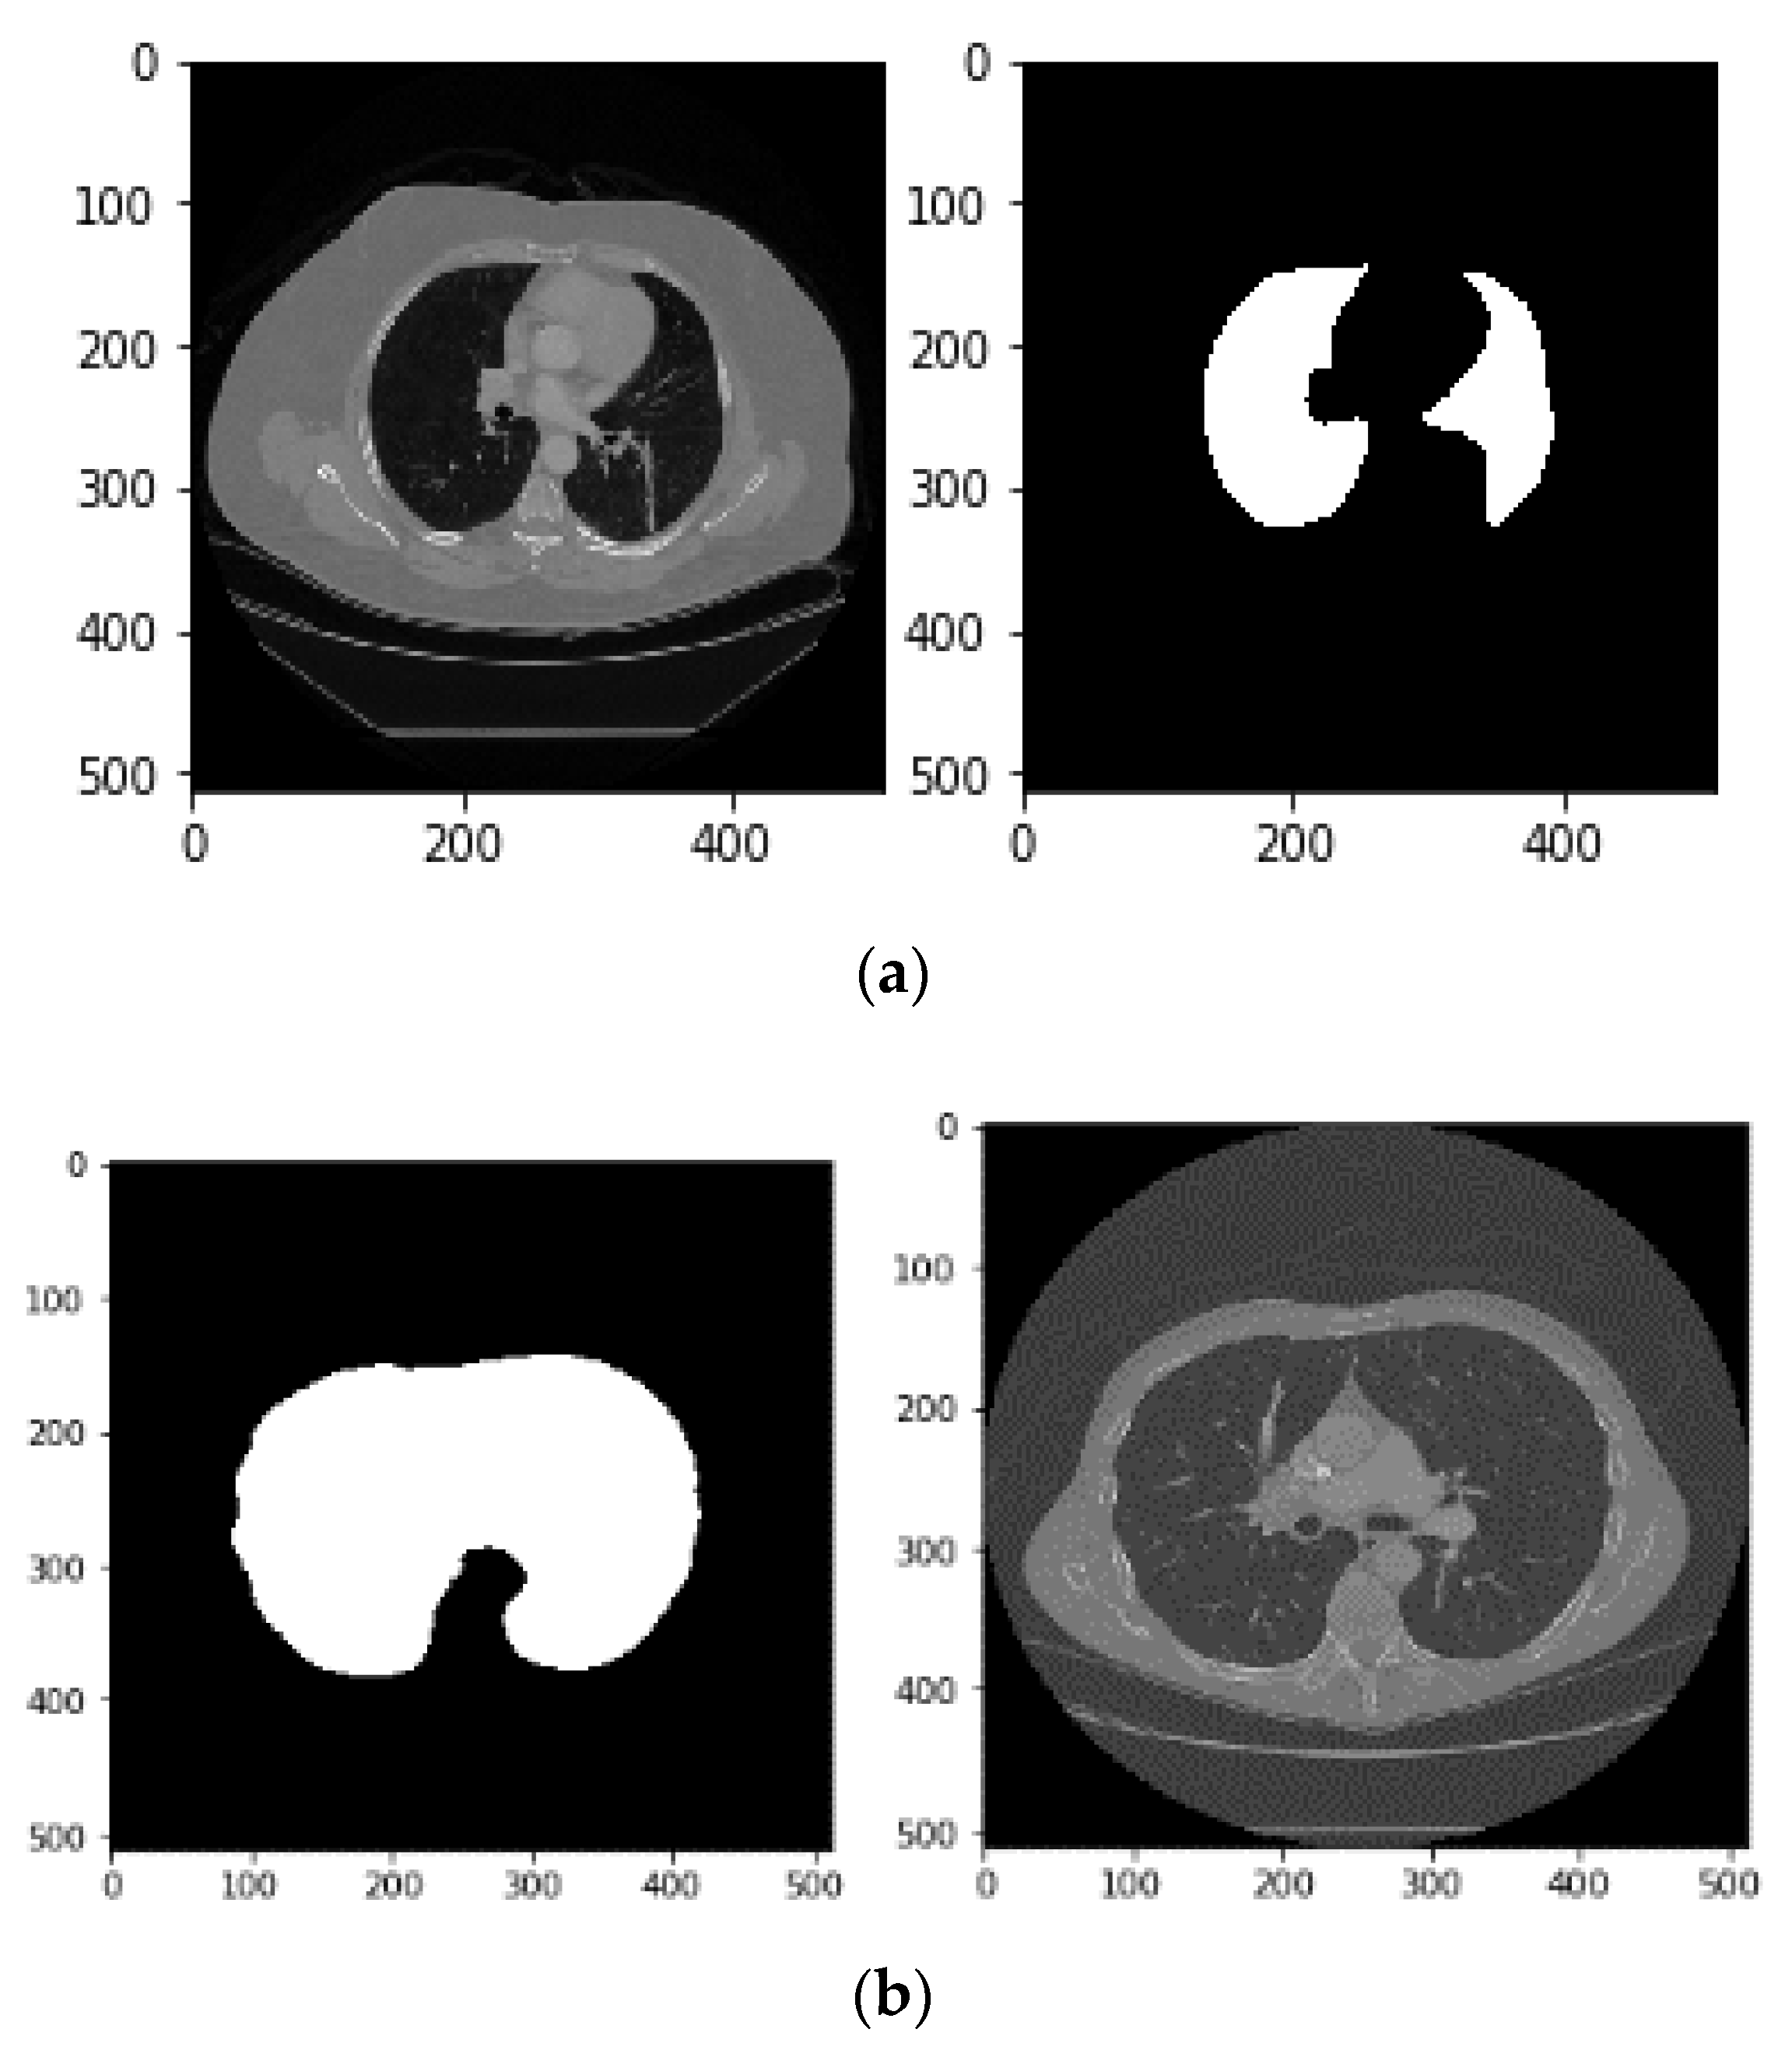

- Image binarization: In this process, a binary image is created with two values on the grey surface, i.e., black and white. The lung region poses a black colour with the value zero. Figure 8 shows the binarization process of a CT image.

- Dilation morphological operation: Morphological operations, typically applied to binary images, are used to extract and describe the geometry of the object in the image [49,50]. As a result of the binarization process described before, there would still be remaining regions of white colour around the lungs regarded as unwanted noise. Thus, morphological operations can be used to remove these regions. Moreover, there could still be some small black holes in the lung’s region, suspicious of noise caused by the binarization process. These holes should be also removed using morphological operations.